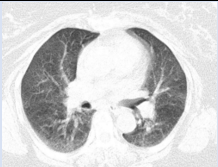

Baseline [18F] F-FDG PET -CT scan was done in the light of confirmed biopsy to assess locoregional nodal and distant metastasis. The study demonstrated increased FDG uptake in the left breast mass with skin, posterior chest wall involvement, multiple small satellite lesions, bilateral axillary and retropectoral lymph nodes (Figure 1 and 2).

Figure 1: FDG PET MIP projection, three lesions were seen demonstrating intense FDG uptake in the chest.